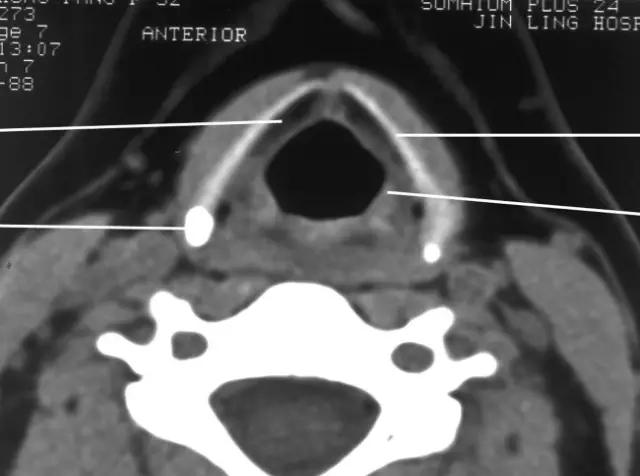

2、CT

1、常规采用横断面扫描,喉腔中轴与扫描线垂直;

2、扫描范围自环状软骨下缘至下颌角会厌上缘,层厚3-5mm;

3、发音状态扫描:让病人连续发“E“音,这时声带内收,可较好显示声带、梨状窝、咽后壁及杓会厌壁的形态及病变。

2、CT、MRI检查

正常喉部CT